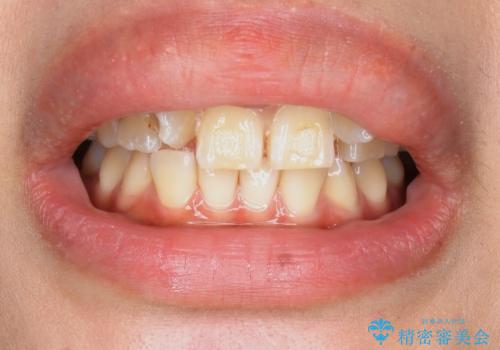

歯の位置異常 はやく治したい 矯正は嫌 20代女性

- 生まれつき上の側切歯と犬歯が逆に生えていることを主訴に来院された患者様です。

他院で矯正を行っていたそうですが、なかなか終わらないため途中で治療をやめてしまったとのことでした。

矯正以外の治療法で早く治したいとのご希望により、上顎両側犬歯を抜去しオールセラミックのブリッジによる補綴治療を行いました。